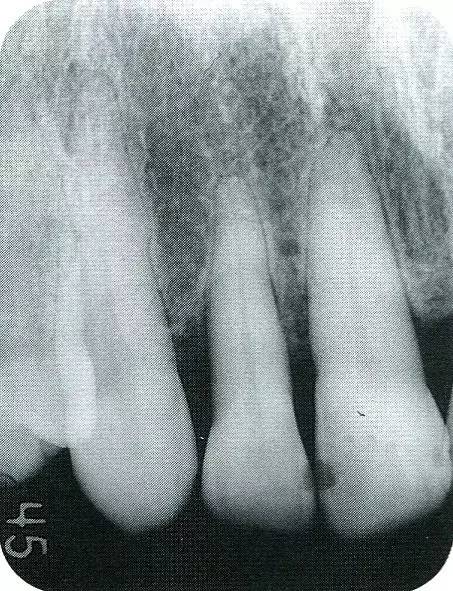

▲圖7-1  左下6近中可觀察到3壁性垂直性骨缺損。此病例考慮到齦瓣供血關(guān)系,在前磨牙部位進(jìn)行了減張切開,沒有進(jìn)行縱切開。并利用刮治器、牙周外科用車針進(jìn)行了徹底的骨缺損部位搔刮。